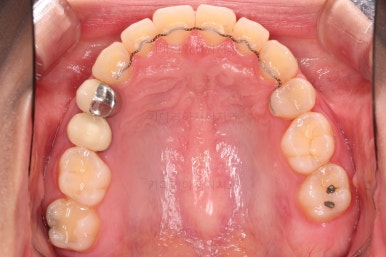

우선 장치를 부착했습니다.

이번에 선택한 장치는 엠파워 클리어라고 하는 자가결찰 세라믹 장치인데요.

흔히 아시는 클리피씨 장치와 같은 분류의 장치입니다. 클리피는 일본, 엠파워는 미국 제조사라는 차이가 있지만 큰 틀에서는 세라믹 바디에 금속 클립이 달린 거의 동일한 장치라고 보시면 됩니다.

부산치아교정 이번 치료의 핵심인데요.

결손 부위에 미니스크류를 이용해서 뒤쪽 어금니들을 결손 부위로 앞으로 앞으로 계속 당겨줍니다.

얼굴모습에서의 중앙선도 지속저으로 체크하면서 한 쪽으로 치우침 없이 마무리를 해야 하고요.

틈새가 줄어들 때 까지 같은 작업을 반복합니다.